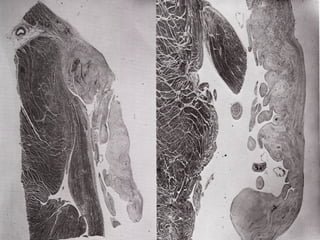

• 53.

Mallory describes that histological features could be determined on gross examination as well:  First 72 hours: Infarction appears pale and drier. Sometimes, hemorrhage is observed.  4 days: Yellow line appears at the periphery due to leukocytic infiltration. Infarct becomes yellow brown.  6 – 8 days: Band becomes broader and sometime yellow-green  8-10 days: Granulation tissue is formed around the infarct forming a reddish-purple zone. Size of infarct decreases, depression may be seen around the infarct  2 – 3 weeks: Healing continues, band of granulation tissue increases and central mass of necrotic muscles decrease. Infarct appears pale and red-brown color.  3-4 weeks: Small islands of necrotic muscle surrounded by granulation tissue.  >1 month: Granulation tissue become older, collagen content increases. Capillaries become compressed and less prominent. Infarct appears paler and gelatinous.  2 – 3 months Infarct contracts to form a white fibrous shrunken and firm scar.